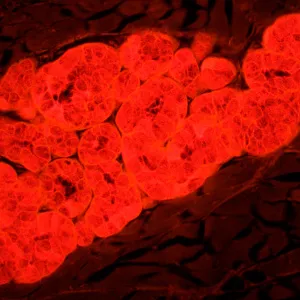

Микроскоп MAGUS Lum 450L – это модель, на которой можно проводить исследования как в светлом поле, так и в свете люминесценции, а при доукомплектовании микроскопа дополнительными компонентами станут доступны и исследования по темному полю, фазовому контрасту или в поляризованном свете. При исследованиях в свете люминесценции MAGUS Lum 450L освещает препарат синим или зеленым цветом – объекты, соответственно, производят зелено-желтый или красный свет. Люминесцентные микроскопы применяются в медицинских экспертизах, криминалистических или фармакологических исследованиях, в работе ветеринарного контроля и санэпиднадзора. Эта модель оснащена системой «умного» освещения, подстраивающей интенсивность света под характеристики объектива, и ЖК-экраном, на котором можно контролировать параметры работы.

- Для работы в свете люминесценции препарат освещается синим или зеленым светом и производит желто-зеленый или красный

| Флуоресцентный модуль | синий (B), 460–495 нм / 505 нм / 510 нм; зеленый (G), 510–550 нм / 570 нм / 575 нм | |